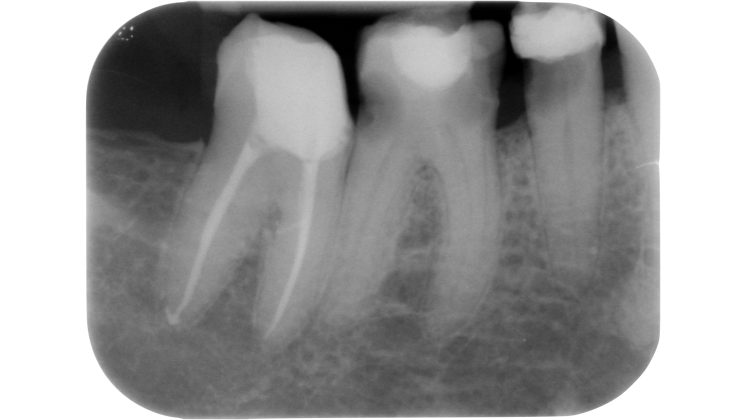

Devono essere valutate con molta attenzione la posizione dell’elemento in arcata e la sua inclinazione (Figure 6-7), l’entità e la posizione del processo carioso se presente, gli eventuali restauri posizionati sul dente e i rapporti con il parodonto: tutte queste considerazioni permetteranno al clinico di capire innanzitutto la mantenibilità e la possibilità di isolare mediante diga di gomma il dente. L’interpretazione degli esami radiografici consentirà inoltre di valutare alcuni parametri preoperatori di notevole importanza:

- presenza di radiotrasparenze periradicolari o periapicali;

- presenza di pregresse terapie canalari e valutazione della qualità delle stesse;